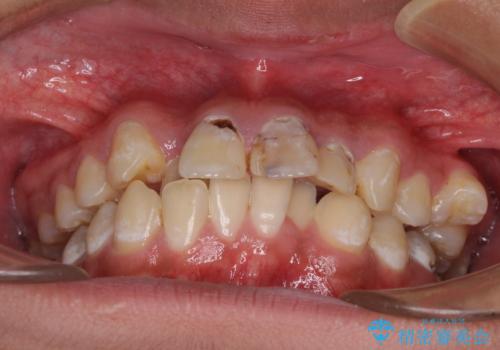

前歯のデコボコとむし歯だらけの歯列 矯正治療と虫歯治療

- むし歯が多く、歯並びも悪いとのことで、以前通院されていたご家族の紹介で来院された患者様です。

口腔内に無頓着であったため、まずはしっかりと歯磨きトレーニングを行い、必要な虫歯治療を行いました。

矯正治療は、むし歯が酷く抜歯が望ましい歯を1本抜歯して、ワイヤー装置にて整えることとしました。